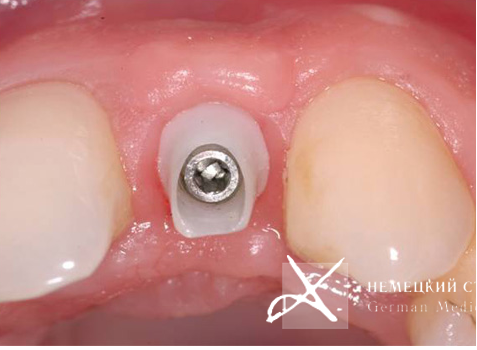

После успешной ортодонтической подготовки и проведенной имплантации в области отсутствующих зубов выполнено последующее эстетическое протезирование.

Учитывая достаточно высокую степень обнажения десны при улыбке, а также тонкий, "просвечивающий" тип слизистой оболочки, для обеспечения максимального эстетического результата выбрана индивидуально моделируемая эстетическая супраструктура (абатмент) на основе оксида циркония, выполненная по CAD/CAM-технологии.